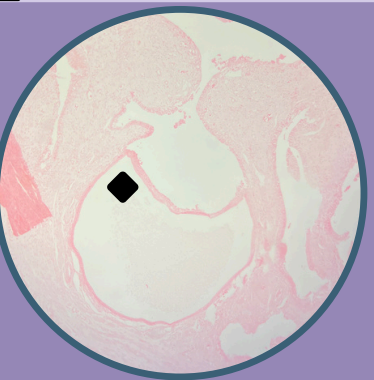

Fibroadenoma de mama:

Proliferación del estroma intralobular

Presencia de ductos comprimidos

Fibroadenoma de mama